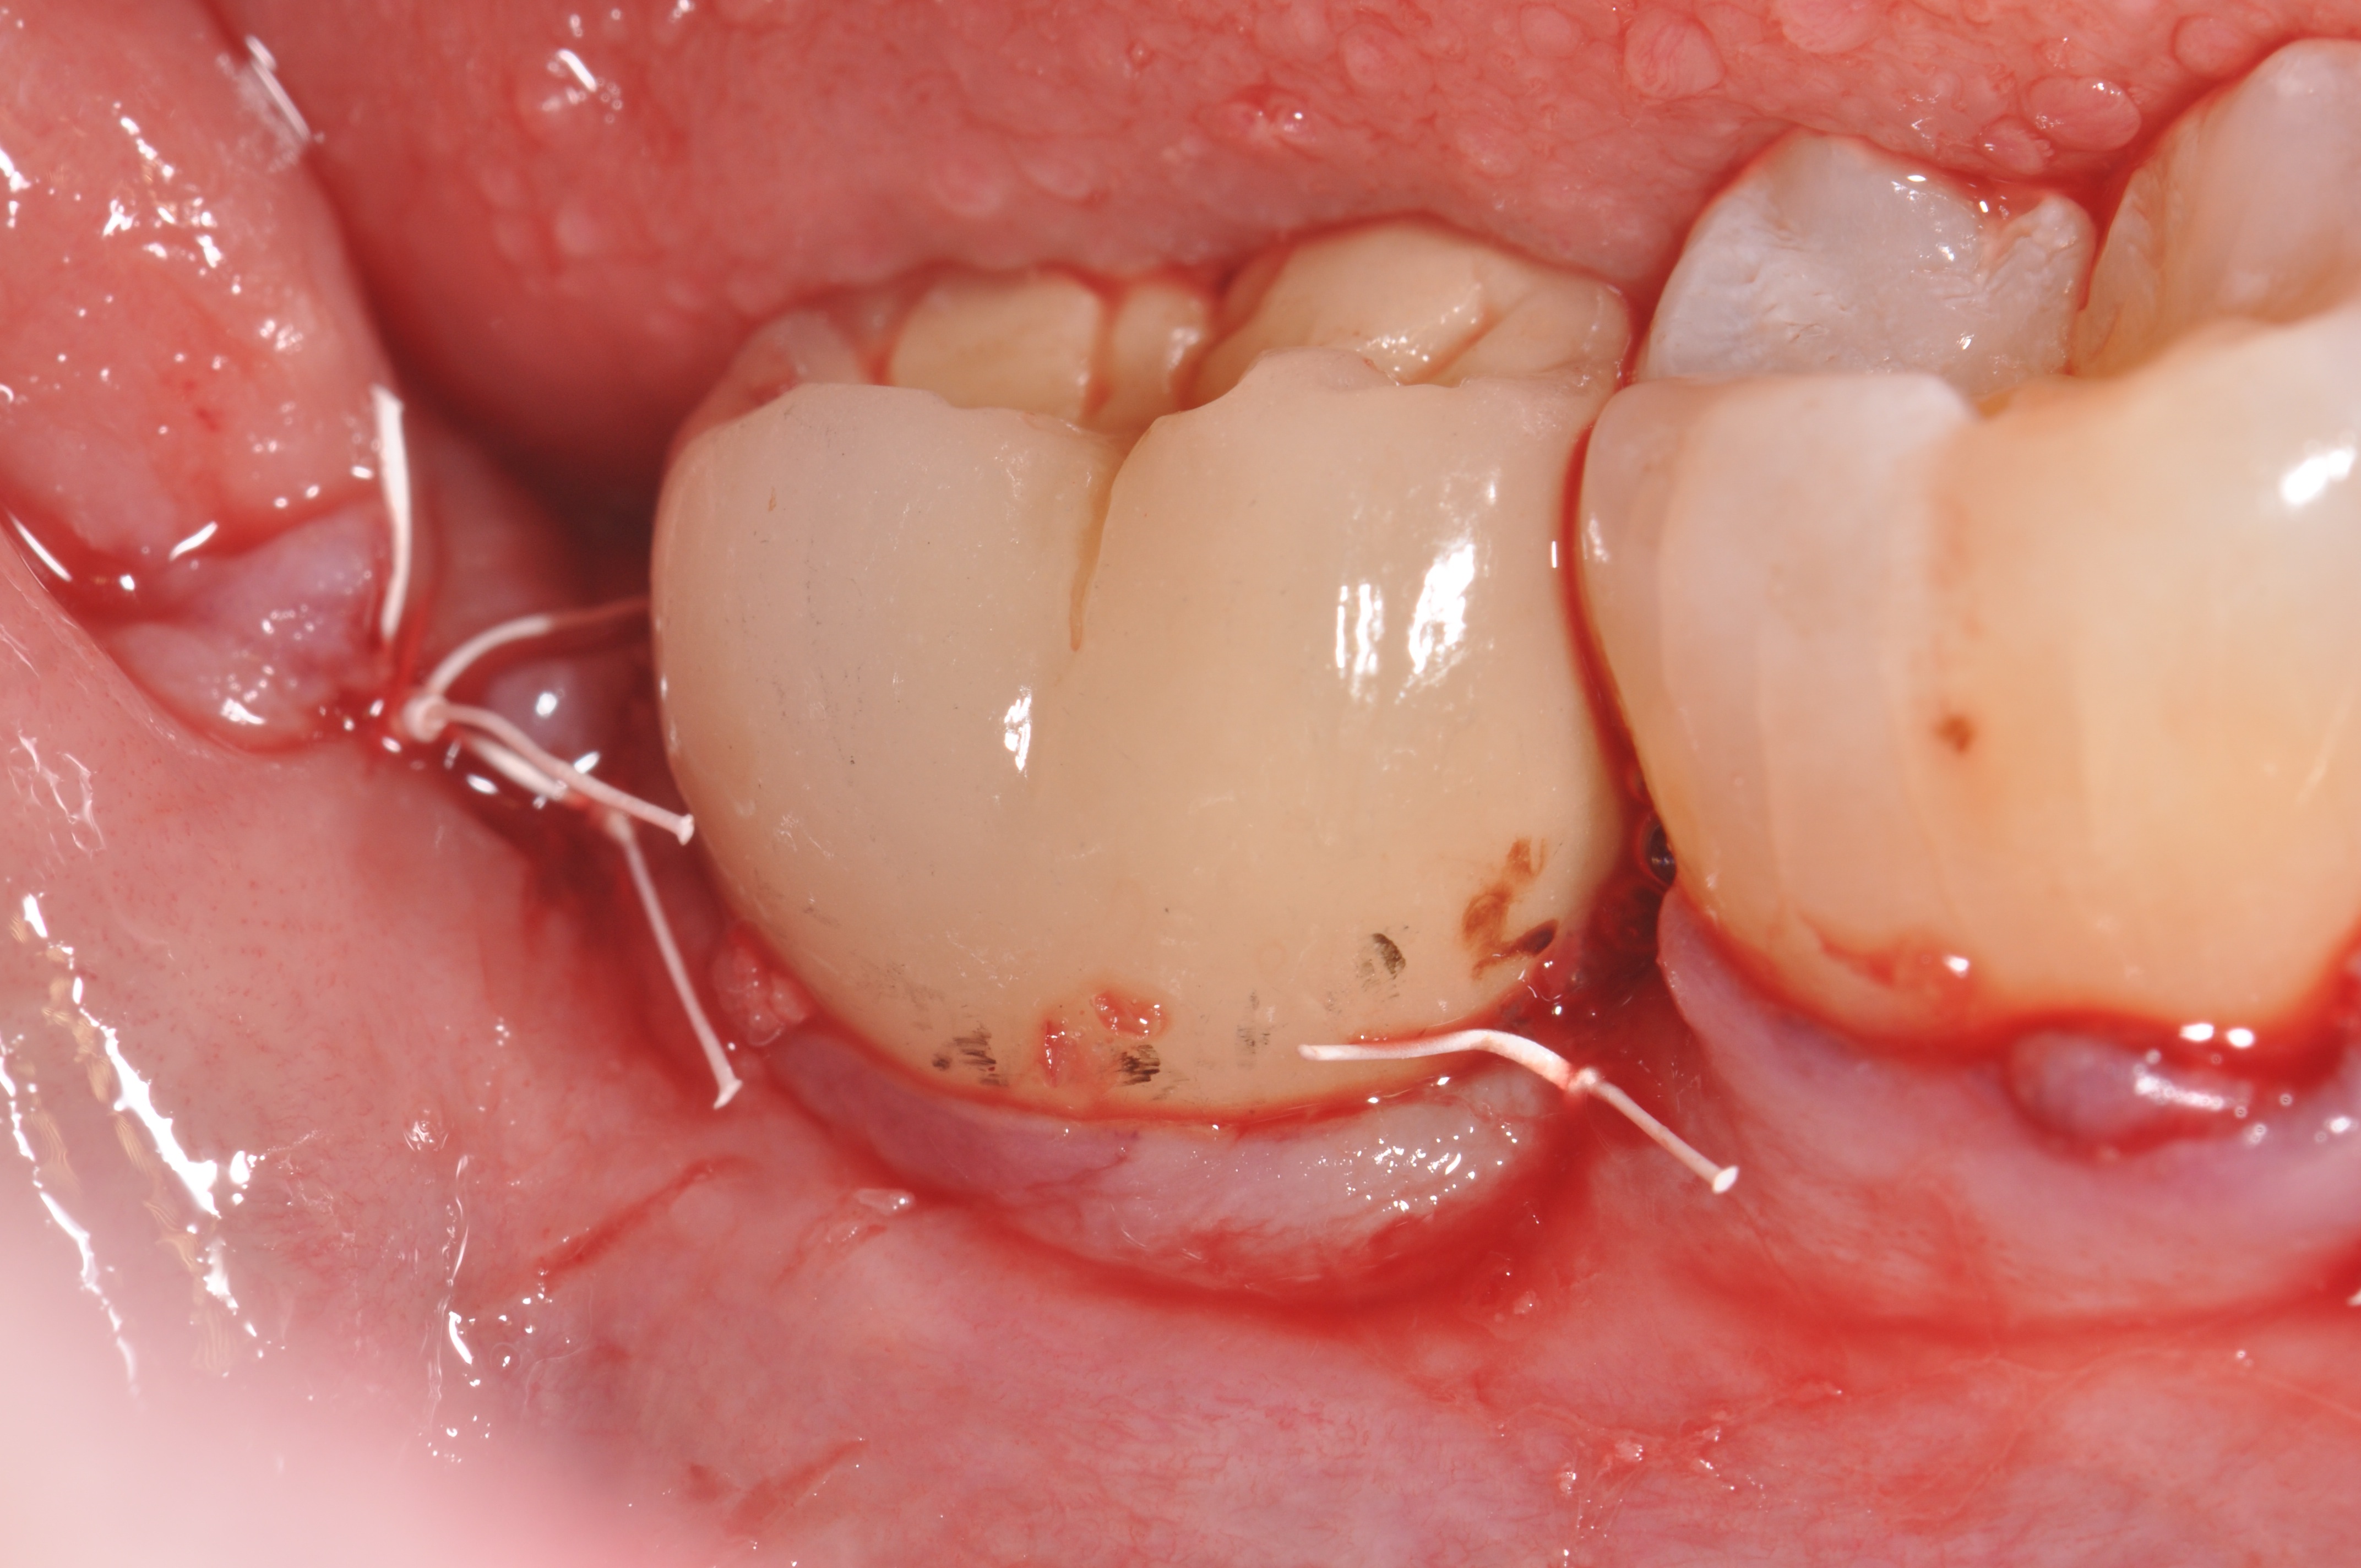

Figure 1

Clinical exposure of a circumferential lesion that demonstrates 3 mm of bone loss. No cement was present, suggesting that the lesion was of bacterial origin. Surface decontamination included citric acid.

Figure 2